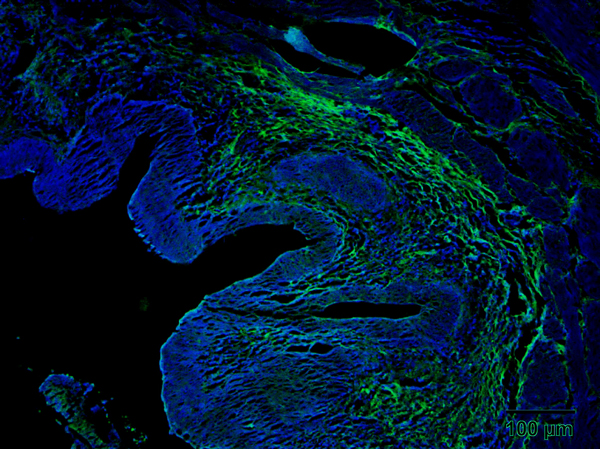

Spinal Cord GFAP Positive Cells